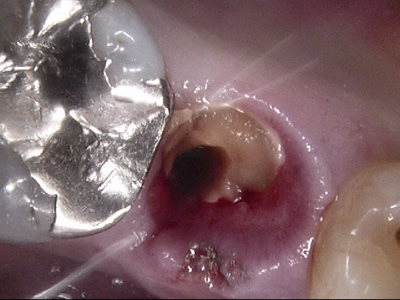

通常では神経まで虫歯が達していた場合、一般的には神経を取る治療になります。虫歯を除去し、神経が露出した場合はMTAセメント(健康保険適応外)の使用することで、神経を温存できる場合があります(生活歯髄温存療法V P T)。

できるだけ削らず、なるべく神経をとらず、なるべく抜かずに治療していきます。例えば、神経を取らないといけないようなむし歯でも、できそうならば、神経を取らずに治療できないか。また、見えている歯が全て虫歯にやられていたとしても根の部分を残せないか?と考えます。

他にも、むし歯になっている部分が染色される、う蝕検知液などを使用し、可能な限りむし歯になってしまった部分だけを取り除き、健全な部分は残すような治療をしています。